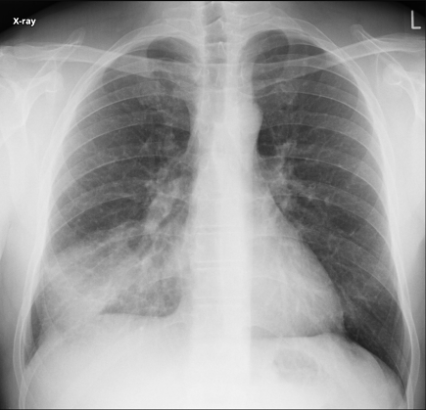

Diagnose?

A

Venstresidig basal pneumoni